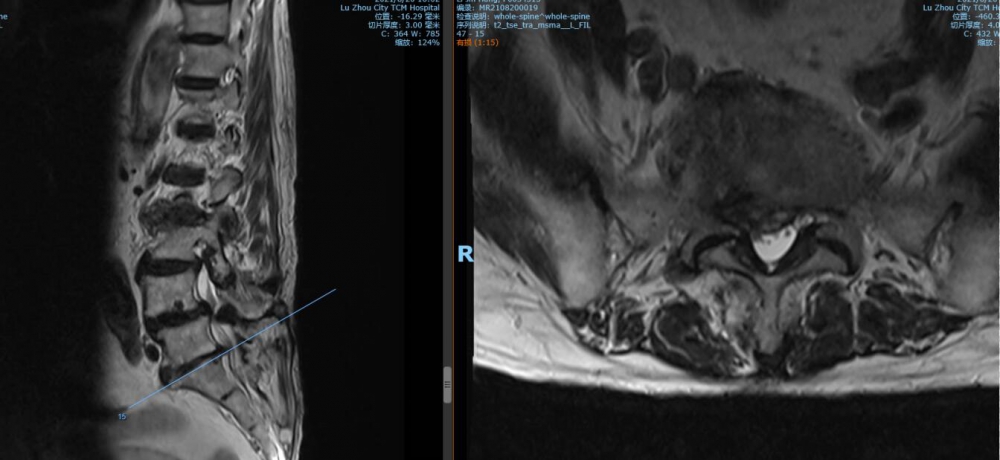

腰5 骶1椎间盘CT

腰5 骶1椎间盘MRI

泸州市中医医院骨伤二科主治中医师胡建超介绍,李谨行老人患有腰椎管狭窄症 、腰4椎I°滑脱 、脊柱退行性侧弯畸形 、冠状动脉粥样硬化性心脏病、心律失常、高血压2级等17种疾病,同时处于慢性阻塞性肺病加重期和脑梗塞恢复期。92岁、全身多种疾病,随时可能会有突发情况,要做这样一个大手术,对医生和患者来说,无疑都是一个巨大的挑战。